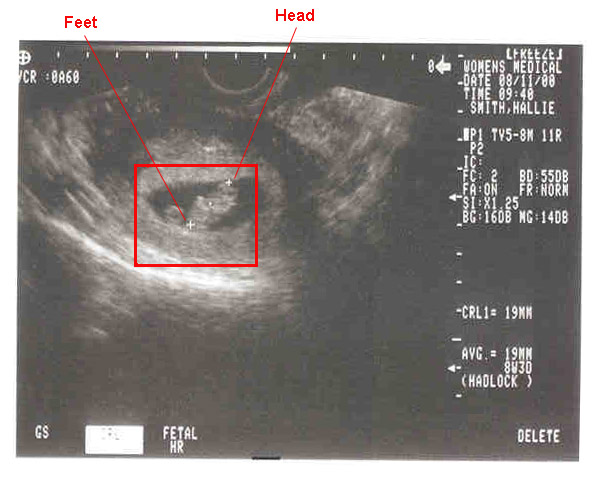

08/11/2000--Internal ultrasound picture at 8 weeks.